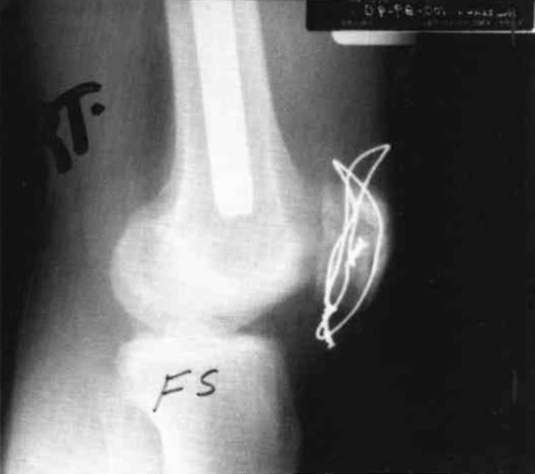

An eighteen year old male sustained bilateral femur fractures and bilateral patella fractures. The patient underwent bilateral closed inter-medullary (IM) rodding of the femur and the patellas underwent bilateral ORIF (Fig. 15 and Fig. 16). The patient was placed in a free knee Mobilizing Brace on the left leg and attached to a continuous passive motion dynamic suspension system immediately postoperatively. The right leg was maintained in a straight position and in a denotation boot to prevent the fractured femur from spinning on the IM rod. In two days, the left knee had 0-90° of pain free passive motion. Active motion on the right lower extremity was limited to 0-15° of motion. At that time, the patient's right leg was placed in a free knee Mobilizing Brace and bilateral passive motion begun (Fig. 17). Right leg motion progressed to 0-90° passive motion in four days, while the left leg was maintained in the 0-90° range. (This passive motion device, providing bilateral application from one power source, can be adjusted for varying degrees of motion independent of each other by varying the tension on the attachment lines.) Ambulation training began utilizing the bilateral Mobilizing Braces with drop locks in position (Fig. 18). The patient was fully ambulatory with this system, achieved full range of active motion in ten days, and was discharged. Passive motion was maintained for a longer period than normal due to the degree of articular damage to the patellas.

Summary